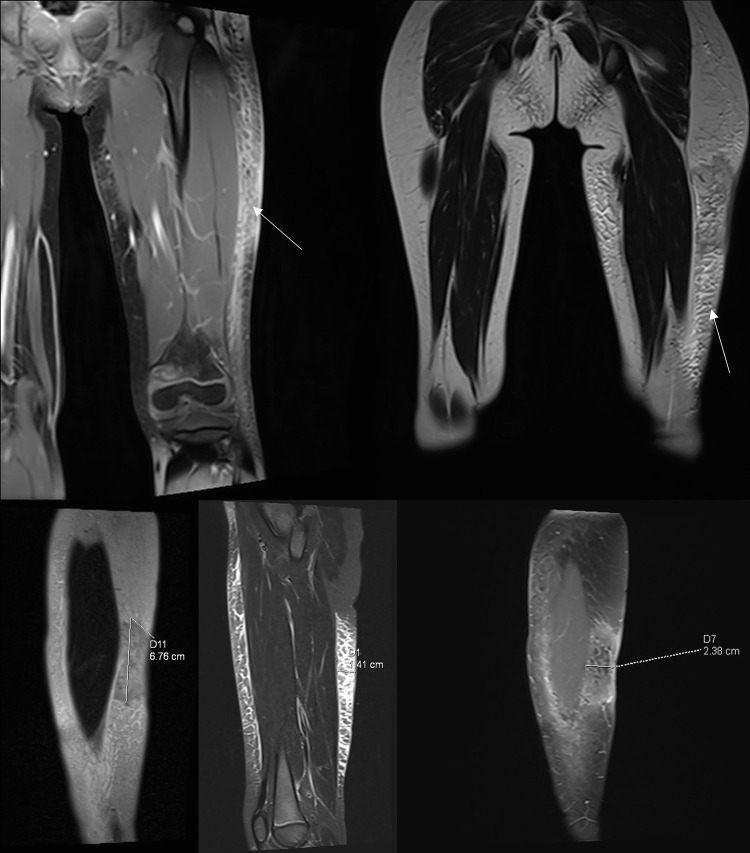

Subcutaneous panniculitis-like T-cell lymphoma (SPTCL) is a rare primary cutaneous lymphoma derived from cytotoxic αβ T cells, clinically and histopathologically resembling inflammatory diseases of adipose tissue, particularly lupus panniculitis. It accounts for <1% of all non-Hodgkin's lymphomas, with approximately 20% of cases occurring in children. The main aim of this paper was to present two pediatric cases of SPTCL, highlighting the diagnostic challenges involved. The first patient, a 5-year-9-month-old boy, was admitted with a 15 cm infiltrative lesion on the left thigh, previously misdiagnosed and unsuccessfully treated with antibiotics. Imaging revealed an infiltrate resembling lymphedema. A biopsy confirmed SPTCL with a typical immunophenotype. The patient received EURO-LB 02 protocol therapy for peripheral T-cell lymphoma, complicated by pancytopenia, respiratory infection, and polyneuropathy. Post-treatment follow-up showed lesion regression, with residual subcutaneous atrophy (5 cm). The second patient, a 7-year-old girl, presented with a 10 cm inflammatory lesion on the left thigh and systemic symptoms. Imaging and histopathology confirmed the diagnosis. She was treated with the same protocol. Three years later, disease recurrence occurred on the left forearm, managed with alemtuzumab and methotrexate. Both patients remain under outpatient follow-up. Despite its rarity, SPTCL poses a significant diagnostic challenge in children. Accurate differentiation and early diagnosis are crucial for prompt and effective treatment.